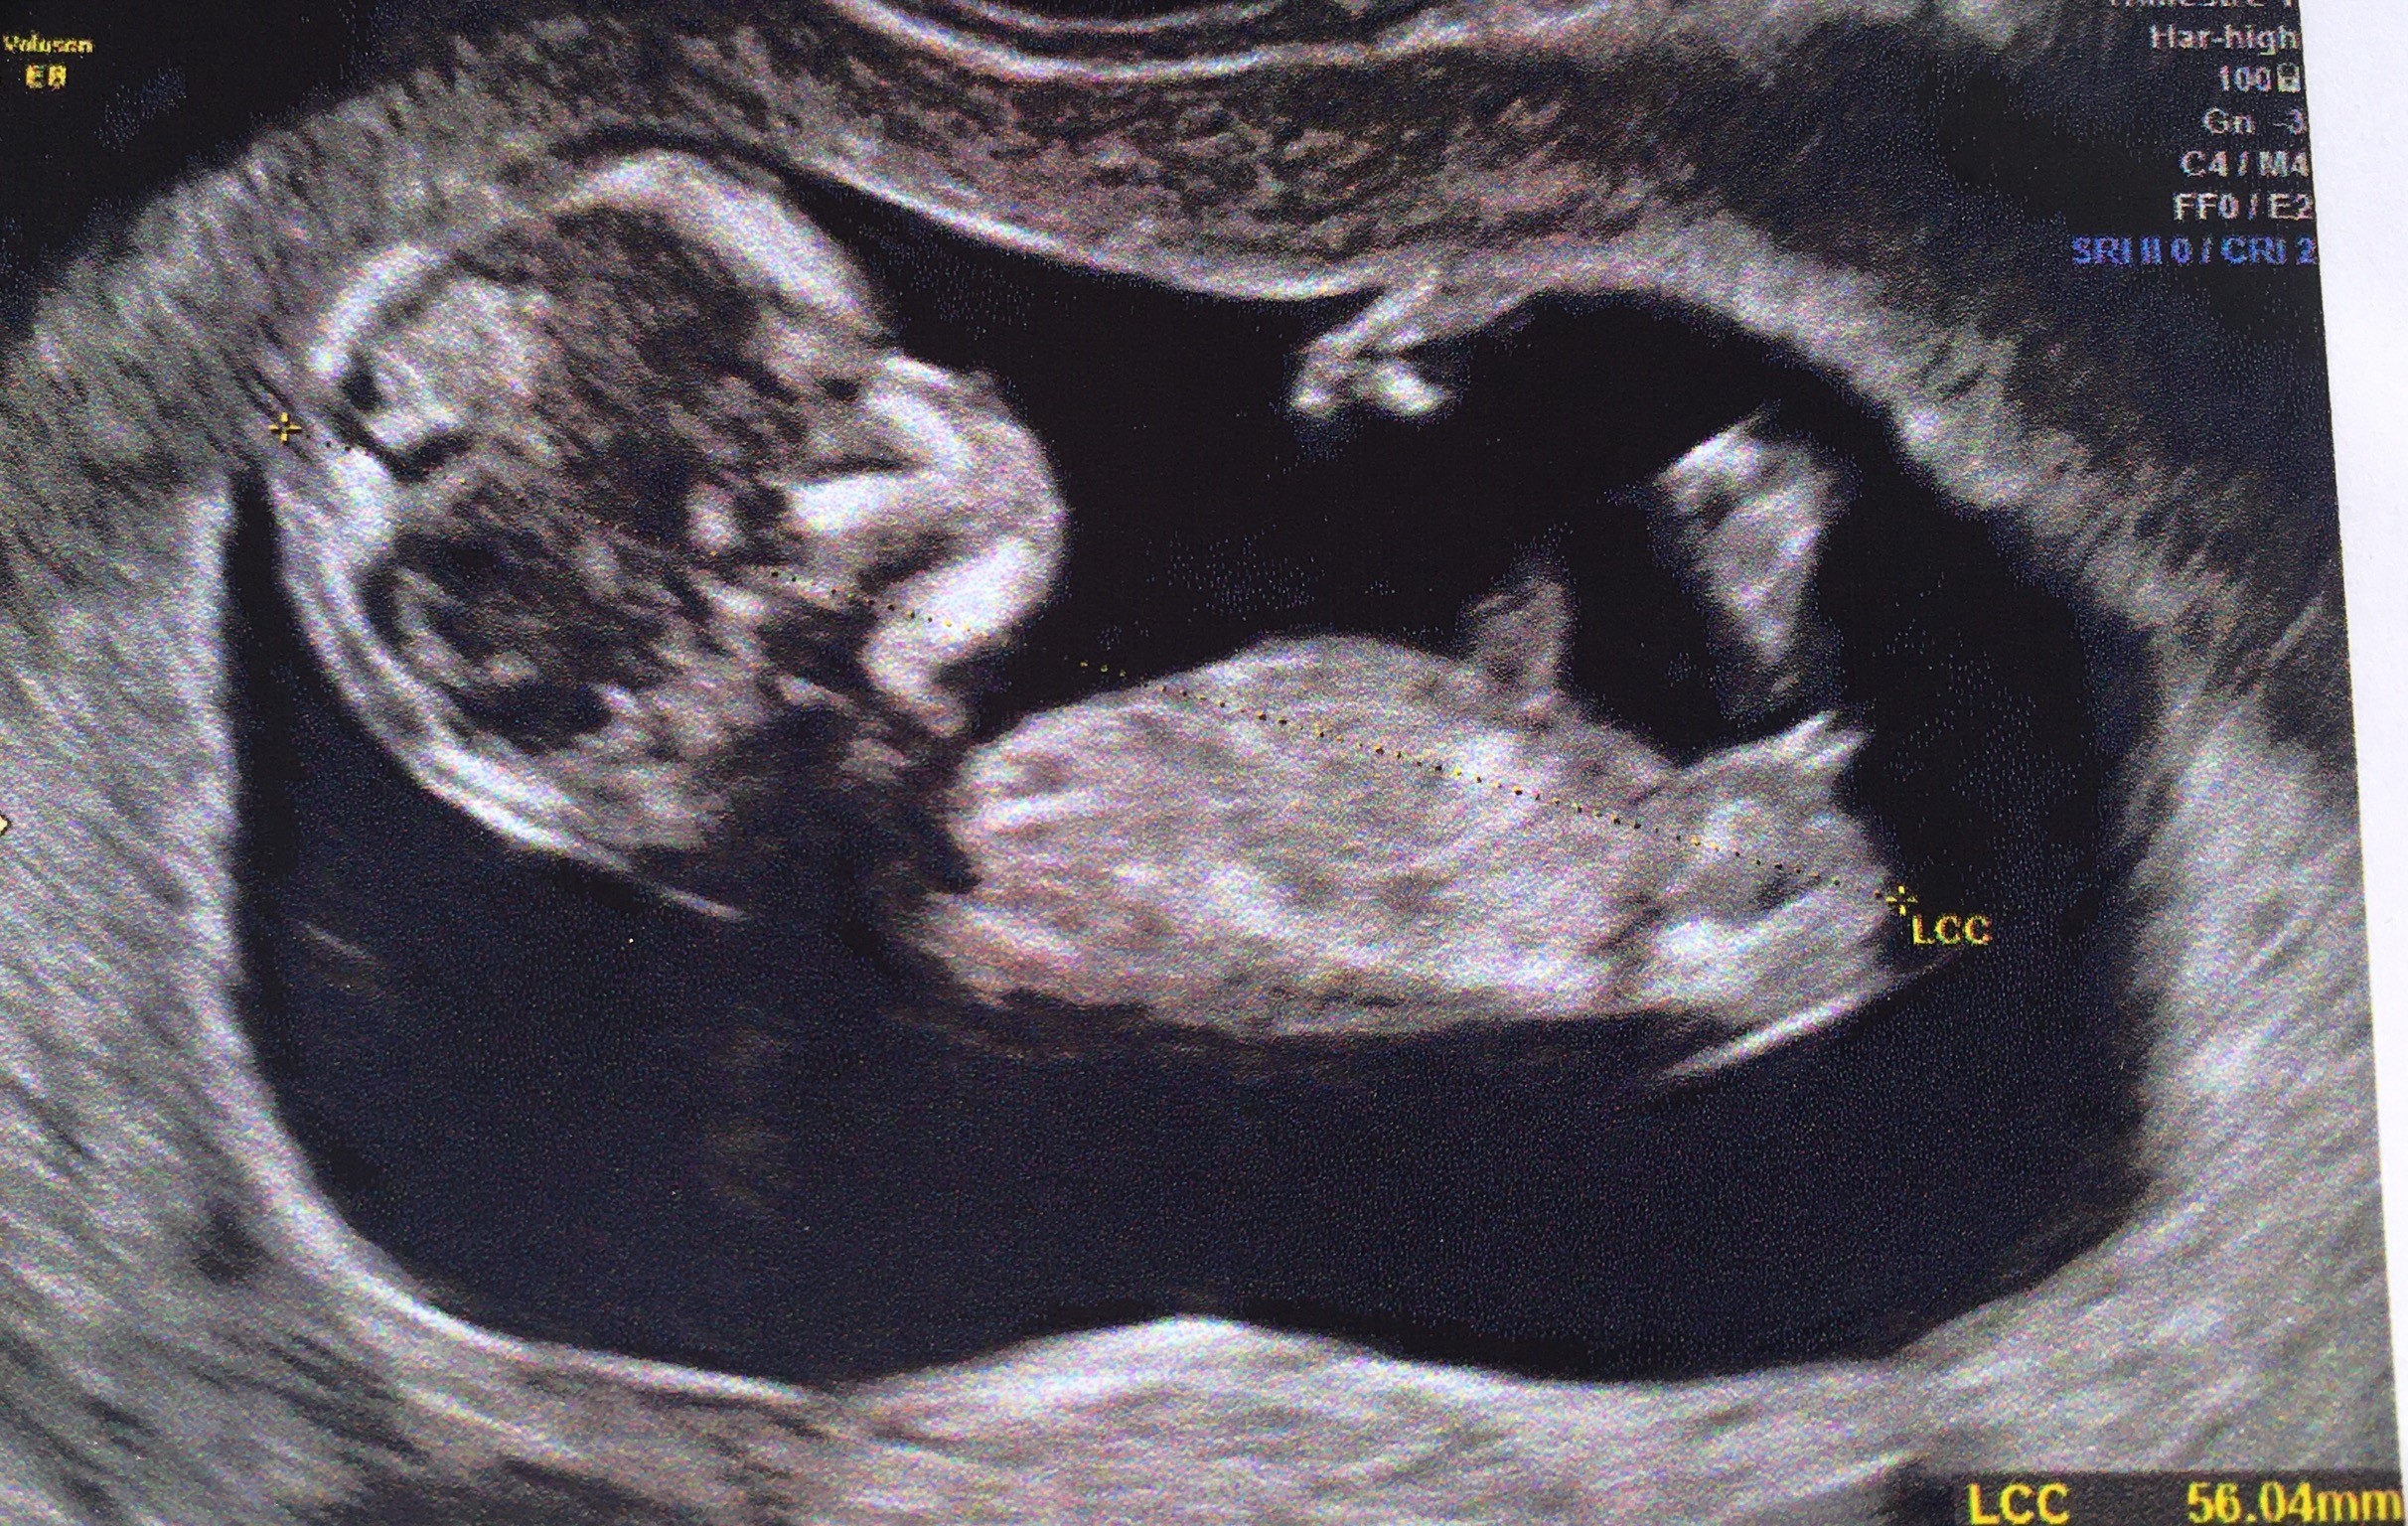

L'échographie du 2e trimestre permet de découvrir le sexe de votre bébé Saurezvous reconnaître s'il s'agit d'une fille ou d'un garçon ?Pour toutes celles qui se posent des questions sur le"bourgeon" et qui ne savent pas patienter, voila des images vous permettant de comprendre la formation du sexe du foetus et ainsi déterminer le sexe des l'écho des 12 semaines Je vous met les images ainsi qu'une série de liens!Pour connaître le sexe du bébé, le moyen le plus fiable reste l'échographie pratiquée entre les semaines 18 et de la grossesse La procédure d'imagerie doit pouvoir indiquer avec une précision de 80% à 90% si tu attends une fille ou un garçon

Les signes de grossesse d'une fille Si le cœur de votre bébé bat à moins de 140 battements par minute, la croyance indique que vous êtes enceinte d'un garçon Les signes de grossesse d'un garçon Si les battements du foetus sont plus vite queDans les 10% des cas restant, le diagnostic de sexe foetal est donc soit impossible soit faux C'est là raison pour laquelle, il est préférable d'attendre l'échographie du 2ème trimester (entre et 25 SA) pour avoir la certitude du diagnostic de sexe foetal qui est alors proche de 100 % à l'échographieLa deuxième échographie, pour connaître le sexe du bébé Serhii Bobyk/shutterstockcom Réalisée entre la e et la 25e semaine d'aménorrhée, la deuxième échographie permet de visualiser l'anatomie complète de votre enfant La croissance, la position et l'aspect du placenta, la quantité de liquide amniotique font aussi l

Il faut atteindre un minimum de 14 semaines de grossesse (plus précisément 14 semaines d'arrêt des règles) pour découvrir le sexe du bébé Avant cette date, le développement du fœtus ne permet pas encore de différencier le sexe L'échographie morphologique pour découvrir le sexe Souvent, c'est lors de la 2e échographie (entreAvant l'apparition de l'échographie, il existait des méthodes plus ou moins étranges et fiables pour tenter de deviner le sexe du bébé attendu Ces tests à base d'urSi vous souhaitez enrichir le post n'hésitez pas à me